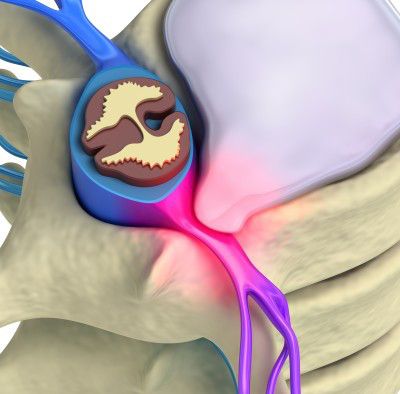

L'infiltration épiduraleet par voie foraminale consiste à injecter un médicament anti-inflammatoire à base de cristaux de cortisone au voisinage du nerf dont l'irritation est responsable de la douleur.

Il s’agit d’un geste habituel et fréquent, non douloureux ; vous serez installés à plat ventre, des images scanner de repérage sont faites, l’infiltration est faite doucement en certifiant le bon positionnement grâce aux images scanner .